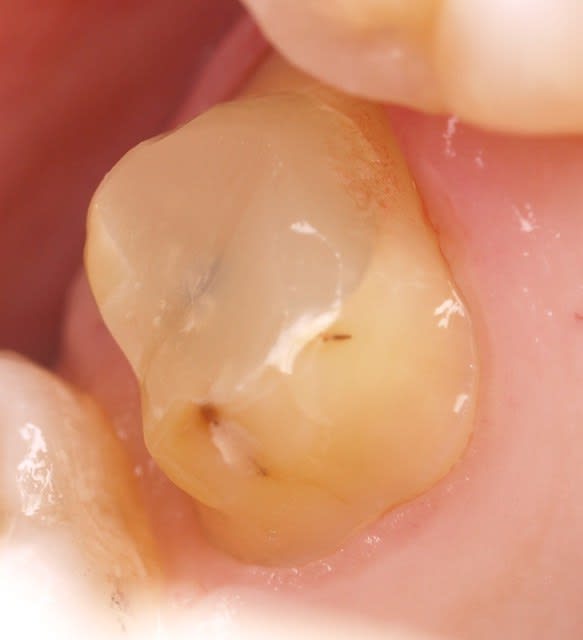

ci joint la photo de la molaire d'en haut le jour du scellement.

ha la voilà

16 i9zdkt - Eugenol